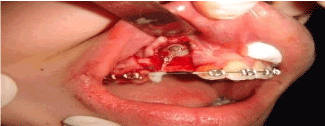

A 12-year-old female came to the dental clinic in the private sector with a chief complaint of unpleasant smile as the upper lateral incisor is flared and missed upper right canine. During our discussion with the patient, her humble request was not to lose any of the permanent teeth. On clinical examination, it’s found that #12 is labially proclined, retained upper right primary canine with slight soft tissue elevation in the labial sulcus on palpation. Intraoral photographs showed misalignment of teeth with shifted upper midline to the right side (Figure 1). A poor oral hygiene had been noticed with a generalized mild upper and lower gingivitis. Panoramic radiograph showed impacted #13 which is overlapping the apical 1/3 of the lateral incisor with retained primary canine (Figure 2). The mesial surface of the canine is passing the root of the lateral and almost flushing with distal surface of the apical third of the central incisor. Periapical radiograph in different horizontal directions (SLOB) techniques along with the palpation and the labial proclination of the lateral incisor confirmed that the impacted canine is labially located. Lateral cephalogram revealed that the incisal edge of the canine is labial to the roots of the incisors. Cephalography analysis documented that patient has skeletal class I malocclusion with decreased anterior facial height and relatively proclined upper and lower incisors. The soft tissue analysis showed that upper and lower lips are relatively behind the Esthetic line (E-line) by 4mm for the upper and 3.6mm for the lower (Table 1).

Figure 2. Pre-orthodontic intra oral digital photos

0.022 slot Roth brackets had been bonded on all upper and lower teeth except #12 which acted as a free body initially till the canine had been moved away from its root (Figure 3). After 6 months of alignment, space started to be created for the canine using opening coil spring (0.010 x 0.035 inch) (Figure 4). The first stage of surgery was planned to be VISTA technique in order to move the canine horizontally and to situate the canine crown directly under its socket using the microimplant (MI) (Figures 5 and 6). During surgery, all the bone distal to the canine crown till its CEJ which is in the way of its movement had been removed. A microimplant from (Ormco) VectorTas of 2 x 8 mm had been placed in the infrazygomatic crest parallel to the upper right first molar (Figure 7). A lingual button bonded on the labial surface of the canine and connected to the microimplant via a power chain which was passing under the alveolar mucosa over the canine. The horizontal movement of the crown had been activated every month by cutting a hole from the power chain. A panoramic periapical radiograph A-B taken directly after MI placement and 3 months over that to control the movement of the canine (Figures 8 and 9). After 3 months of horizontal movement of the canine, the patient referred again for the 2nd stage of surgery where a full reflected flap performed in order to remove the old power chain and place new one which is directly connected to the main archwire (Figure 10). All the bone above the canine crown till the 2 mm from the alveolar crest had been removed in order to facilitate the tooth movement vertically. The main arch wire which is 0.017x0.025 Stst had been offset in the area between #12, 14 (Figure 11). This offset placed to help for keeping the canine root in the alveolar bone and avoid the labial tipping of the crown. A crimpable attachment with a hook fixed on the wire directly over the canine crown and a power chain connected directly from the lingual button to the hook (Figure 12). The vertical movement of the crown had been activated every month by cutting a hole from the power chain. After the canine came out of the soft tissue a bracket bonded and thin wire placed in its slot with a sequence of 0.12 Niti, 0.14 Niti, 0.16 Niti, 0.16 x 0.22 Niti, 0.16 x 0.22 Stst, 0.17 x 0.25 Niti and 0.17 x 0.25 Stst. Canine root torque had been checked after its reaching to the occlusal plane and found that no need for any adjustment since it is similar with the opposing canine root eminence (Figure 13). After 24 months of active treatment, all appliances were debonded (Figure 14). Orthopantogram, lateral cephalography and periapical radiograph had been taken to record as a baseline for future follow up and assessment. Clear overlays delivered for both arches as retainers with proper instructions (Figure 15).

Figure 4. Intra oral photos of the stage of creating space for the impacted #13